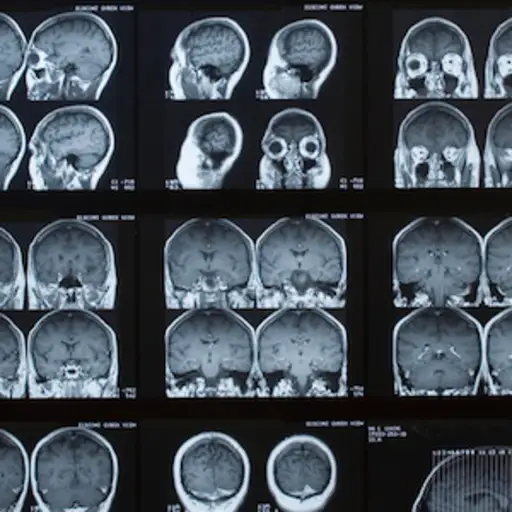

所以抑郁症是一种大脑疾病?

以一种说话方式。更准确地说,抑郁症是大脑在应对任何生命的情况下抛出我们的方式的失败。在这方面,我们正在谈论在我们的生物学和环境之间复杂的互动中的崩溃。

确定。我们的“本性”可能是某种遗传的易患压力、忧虑、缺乏动力或其他任何可能导致抑郁的精神状态。在生物学层面上,这可能涉及到大脑的某些区域或它们的连接回路有被过度刺激或过刺激的倾向。

等等,你说的刺激过度还是刺激不足是什么意思?

边缘系统可能对我们周围发生的事情过于敏感或不够敏感。我们的额叶皮层可能也有类似的缺陷。当一切正常运转时,我们的情绪会激发我们的思考,而思考又会调节我们的情绪。当事情出错时,我们的过度情绪要么压倒了我们的想法,要么我们的过度想法对我们的情绪有负面影响。

别担心。专家们也是如此。把大脑想象成一个复杂的生态系统,在这种情况下,大脑由1000亿个神经元组成,有100万亿个连接,它们组成一个整体,与周围的一切相互作用。当一件事出错时,很多事都会出错。影响是全球性的。这就是为什么认为抑郁症仅仅是“大脑的化学失衡”是危险的。